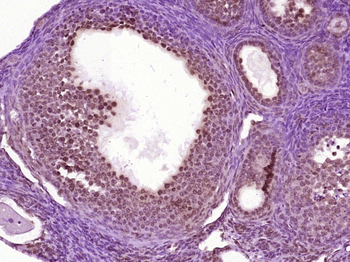

Nanog Rabbit Polyclonal Antibody抗体

Nanog Rabbit Polyclonal Antibody

NANOG

IF, IHC-Fr, IHC-P

KLH conjugated synthetic peptide derived from human Nanog (21-120/305aa)

应用稀释比例:IHC-P=1:100-500, IHC-F=1:100-500, IF=1:100-500